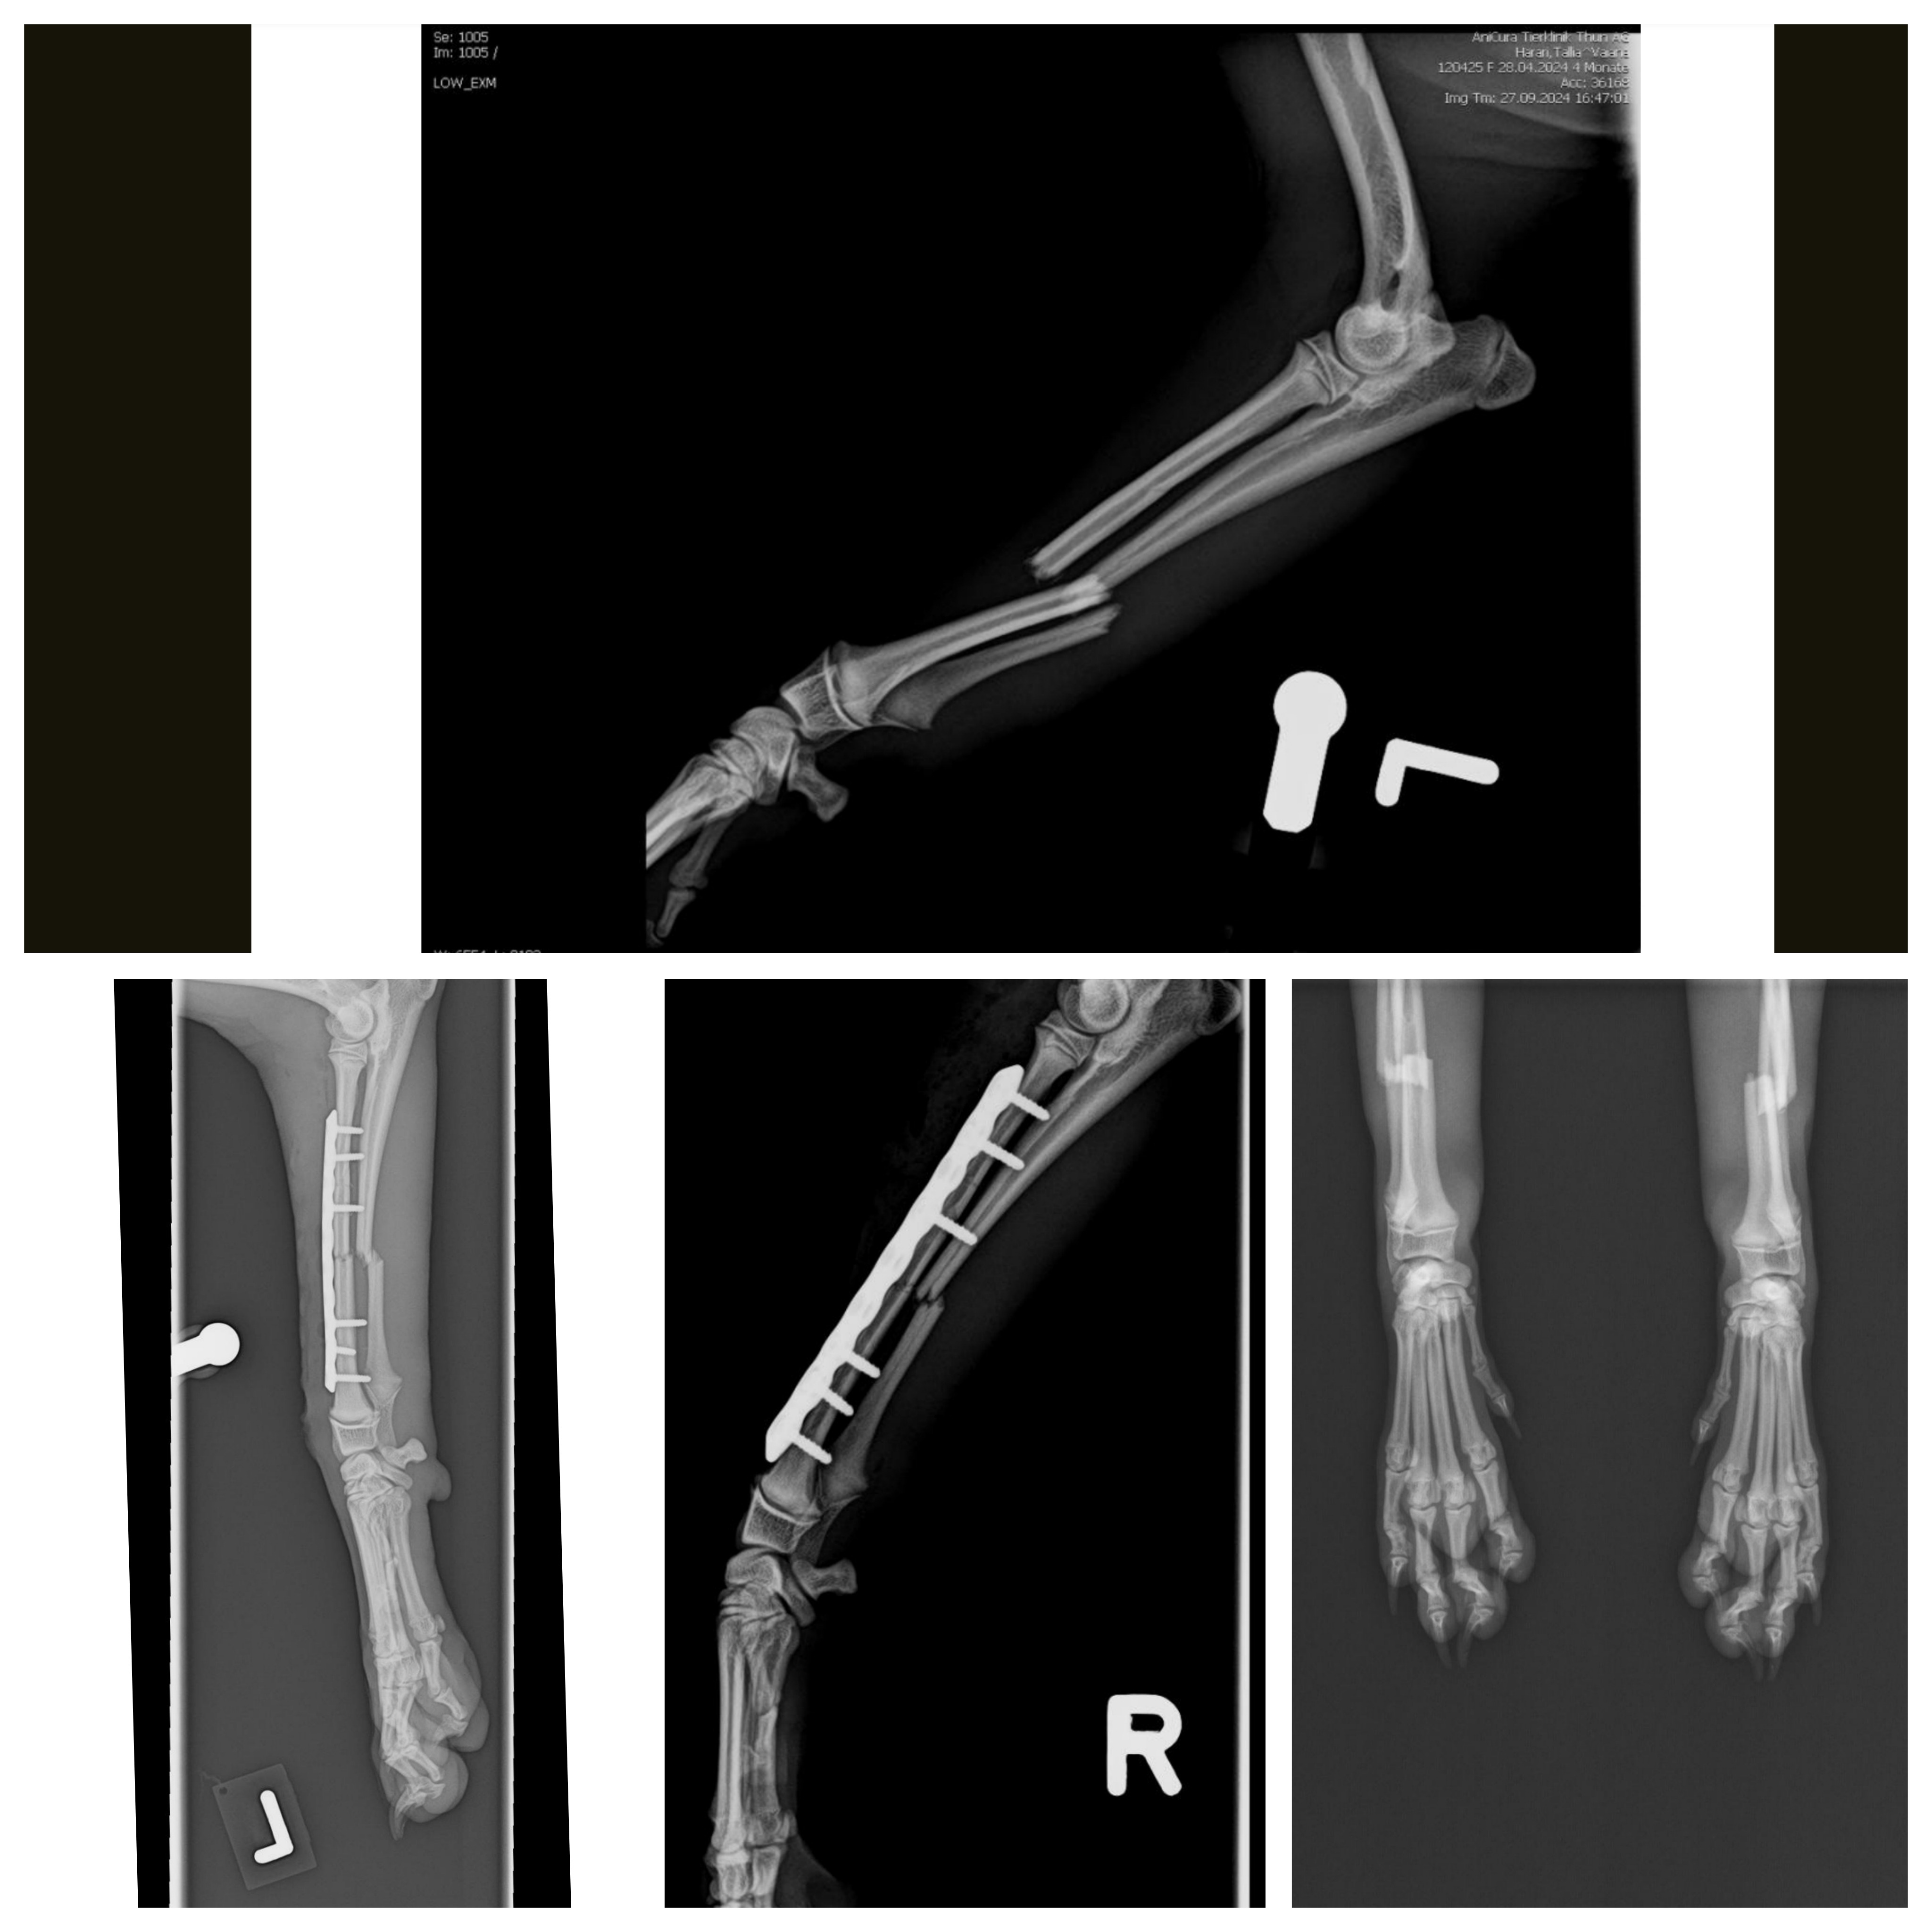

Mit 5 Monaten erlitt sie leider einen schweren Unfall. Sie ist im Wald gestürzt und brach sich beide Vorderbeine. Ich höre ihre Schmerzensschreie und Krämpfe nach dem Sturz immer noch, und die Bilder, wie ich sie damals in den Armen so schnell wie möglich zum Notfall trug, und ihr grosses Leiden und der Schock, bleiben immer in meinem Kopf.

In der Tierklinik wollten die Ärzte damals aus zeitlichen Gründen (Freitag Abend) nur 1 Bein von Vaiana operieren und das andere Bein dann erst am Montag. Deswegen musste Vaiana schon damals 2 Narkosen ertragen. Danach bekam sie beidseitig eine Platte mit Schrauben ins Bein und durfte für sehr lange Zeit nicht mehr frei laufen, rennen, spielen, springen etc. Monatlich mussten wir mit Vaiana in die Tierklinik, um die Beine zu röntgen und wöchentlich den Verband wechseln. Danach musste sie immer wieder mal eine OP überstehen, um ein paar einzelne Schrauben der Implantate entfernen zu lassen, welche beim Wachstum der Knochen gestört haben. Bis jetzt musste Vaiana schon 6 grosse Operationen mit Narkosen erleiden. Einmal hatte sie Mühe beim Erwachen nach der Narkose in der Tierklinik. Sie ist von all diesen Eingriffen in ihrem jungen Alter ziemlich geschwächt und erschöpft.

Nach über einem halben Jahr mit Einschränkungen und Leiden, war endlich die letzte Operation für Vaiana Anfangs Mai 2025 geplant, um die letzten restlichen Implantate rauszunehmen. Mit Schrecken stellte der Chirurg jedoch fest, dass sich der Knochen beim rechten Bein zurückgebildet hat (vermutlich wegen der Platte, welche noch drin war) und dass der Knochen so dünn geworden ist, dass er schon fast wieder bricht. Nun hat sie seit ein paar Wochen beim rechten Bein wieder einen Schienenverband und die ganze Prozedur beginnt von vorne!!! Es nimmt einfach kein Ende und die Behandlungen gehen weiter... Das linke Bein ist zum Glück wieder relativ stabil geworden. Jezt hat sie wenigstens 3 Beine statt nur 2 Beine, welche sie belasten kann.

Diagnose: Radius und Ulna Fraktur diaphysär beidseitig

Implantate: Lockingplatten mit Schrauben